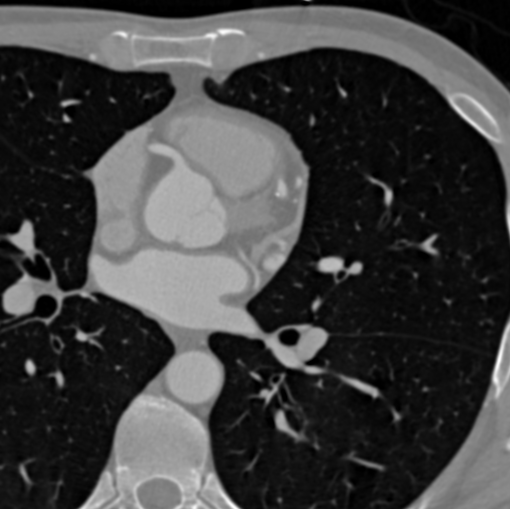

Example of a DICOM Image